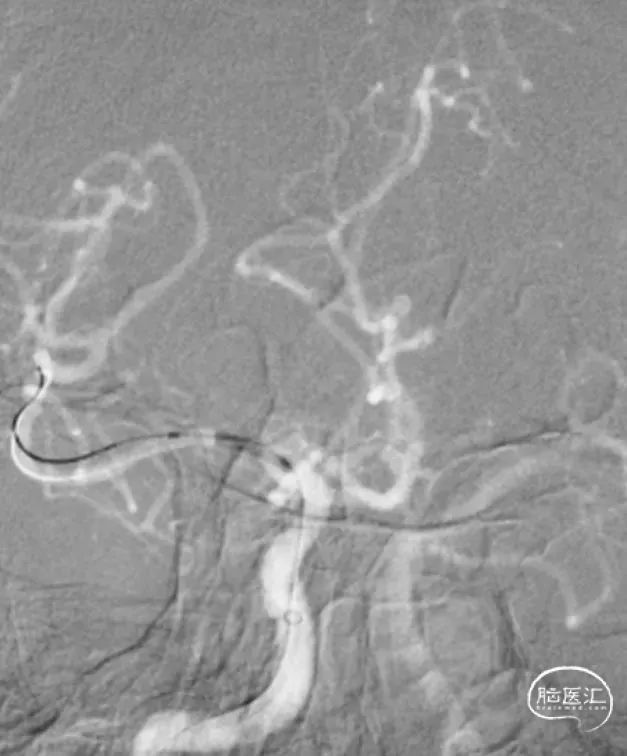

治疗过程

路图下,泥鳅导丝引导132cm Simmons II导管至右侧颈内动脉C1段,跟进6F 115cm 通桥银蛇®Plus远端通路导管至右侧颈内动脉C4段。

0.014" 200cm微导丝送入右侧大脑中动脉上干,随后跟进17微导管。

术后影像

术后患者血流恢复良好。